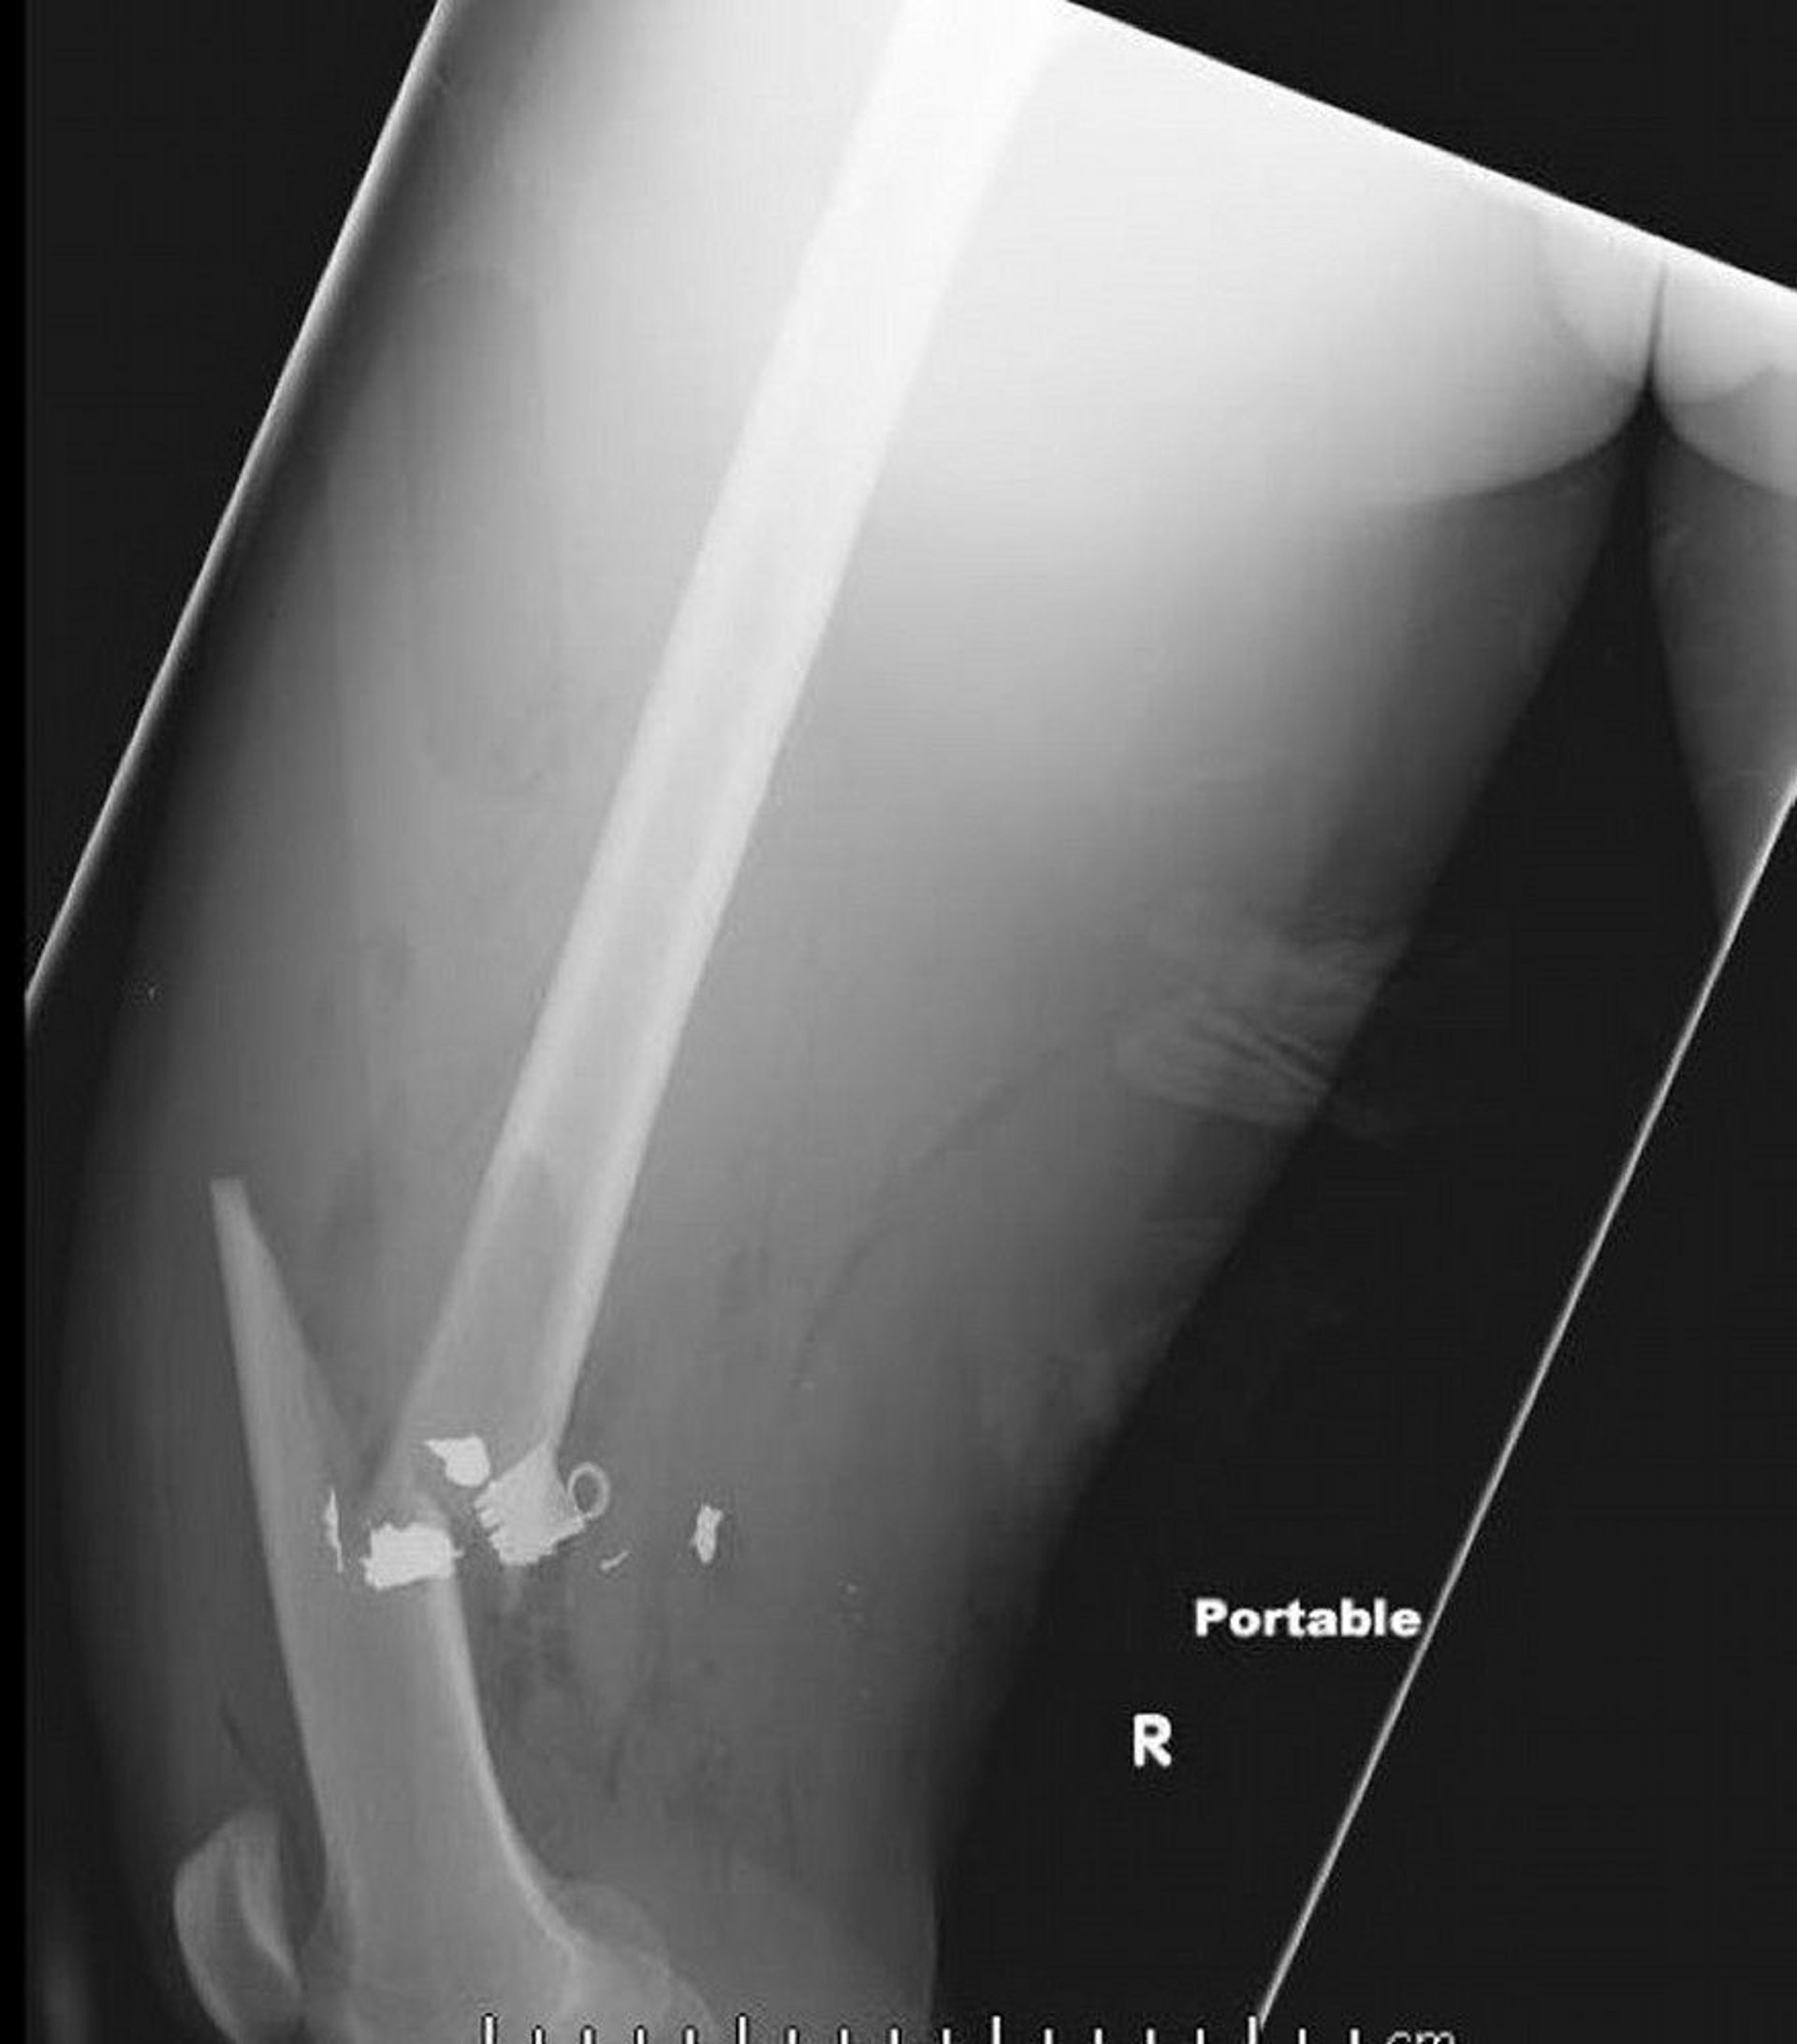

This lateral femur radiograph shows a midshaft femur fracture with soft tissue air and retained metallic density foreign bodies.

Image courtesy of Danielle Campagne, MD.